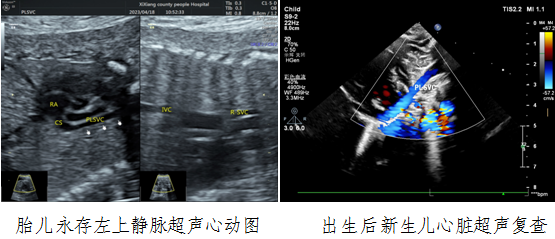

病例一,30岁,孕22w+,G2P1,既往产检未见胎儿心脏结构异常。2023年4月到西乡县医院例行常规产前超声检查,三级片

对口帮扶贾玄慧医生,超声发现胎儿存在先天大血管发育异常——永存左上腔静脉,指导孕妇进行产前咨询及产后随访。胎儿出生后1天,贾玄慧医生立即对该新生儿进行了心脏复查,结果确诊永存左上腔静脉诊断明确。